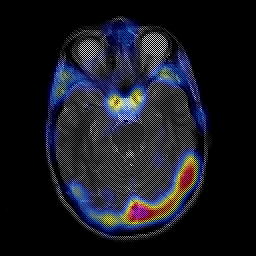

overlay -- Slice #9

[Home][Help][Clinical] Slice 9